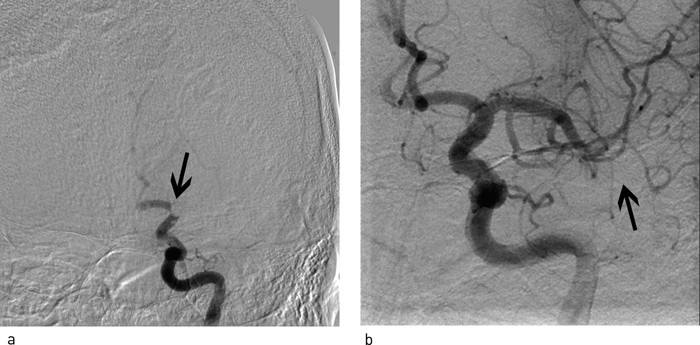

Diagnostisk cerebral angiografi ble utført og pasientens basilarisstenose (fig 2a) samt den kollaterale sirkulasjonen ble evaluert. Det var minimal kollateral blodforsyning fra fremre kretsløp. Det ble gjort tre forsøk med angioplastikk (Maverick II-ballongkateter). Dette ga ikke tilstrekkelig blodstrøm i distale a. basilaris. Man la derfor en Wingspan-stent (Boston Scientific) i stenosen. Stenten bidro til forbedret blodstrøm til det distale basilariskretsløpet. Angiografisk reststenose ble målt til 50 % (fig 2b). Pasienten lå ett døgn i intensivavdeling etter prosedyren før han ca. en uke senere ble utskrevet til hjemmet med mild bilateral dysmetri i overekstremitetene, men uten dysartri eller ataksi. Medikasjonen var den samme som ved innkomst. Etter tre måneder var han restituert til samme funksjonsnivå som før siste hjerneslag, uten nye TIA.